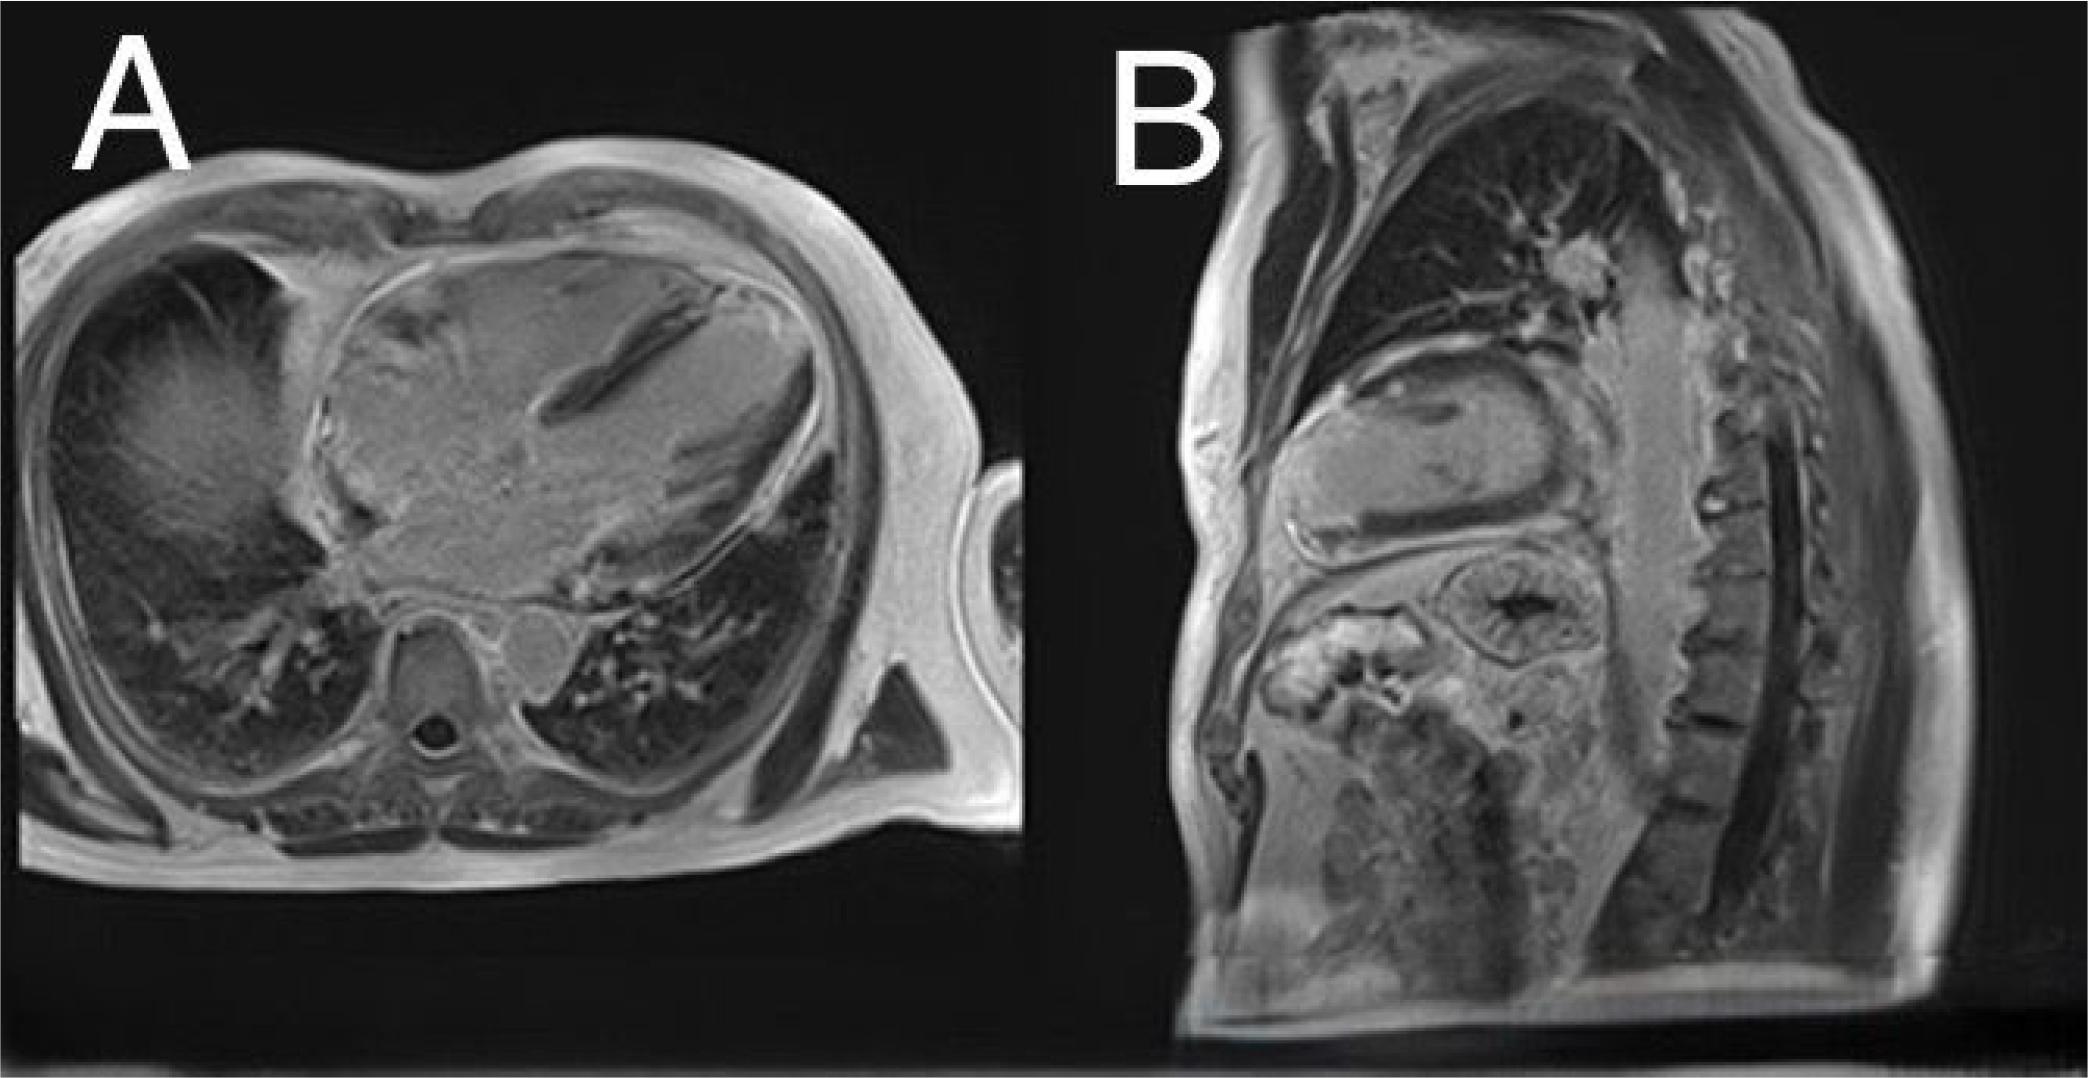

Figure 4